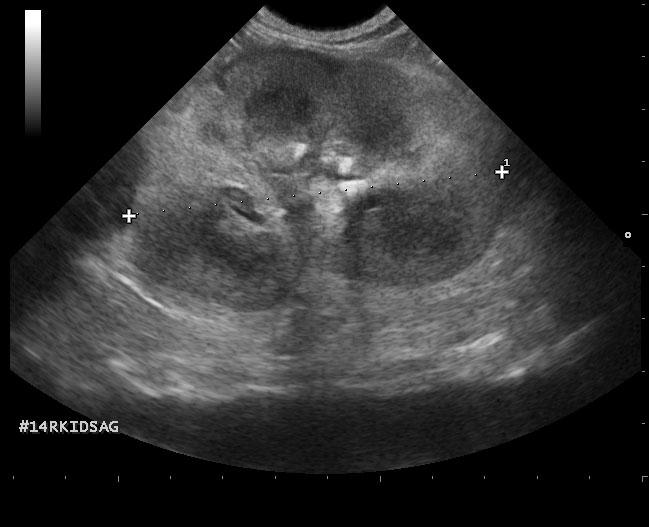

The left kidney was enlarged and measured 5.4 cm with pyelectasia and ill defined fat. Decreased corticomedullary definition was noted with focal capsular expansion at the caudal pole. The right kidney was also moderately to severely enlarged with corticomedullary and pelvic calculi. Loss of corticomedullary detail was noted. Minor subcapsular halo formation was noted with periserosal inflammation. The urinary bladder presented multiple small calculi measuring 0.1-0.3 cm. Mesenteric lymph nodes were enlarged and measured 1.5 cm and 1.8 cm. These lymph nodes were significantly hypoechoic, yet architecture was not distorted at this point. Hyperechoic reactive fat was noted.